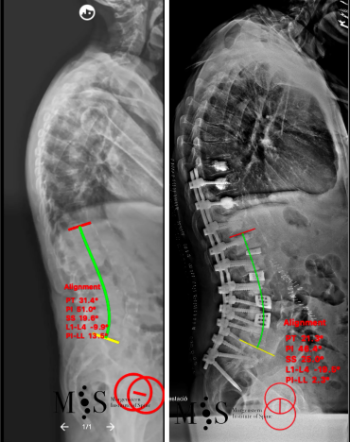

Scoliosis is a deformity/curving of the spine in the frontal plane. It can be congenital (present since birth) or degenerative (developed during the aging process). Progressive degeneration of the intervertebral disks (because of age, weight, activity, etc.) can lead to the spine to deform and curve in, ending up as a degenerative scoliosis, also called "de novo" because it is of "new" appearance in comparison to congenital scoliosis which has been present since birth.

Scoliosis lead to a curved back with the patient having problems walking with a straight back, and it can lead to an intense back pain. The spinal deformity and curving can lead to an impingement of the nerve roots which can cause radiating leg pain.

In these painful cases, surgery is indicated to (partially) correct the deformity and mainly to reduce/eliminate the pain generated by the scoliosis. In the most severe scoliosis cases an osteotomy (chiseling of a vertebral bone) may be required to straighten up the spine and reduce its deformity.

At the Morgenstern Institute of Spine we use the most advanced surgical endoscopic and percutaneous techniques to correct the degenerative scoliosis and speed up the patient’s recovery time. Hospital discharge is usually just a few days after surgery.